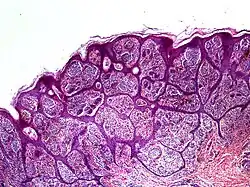

Histology

High-powered imaging tools may identify one or more traits that prove a lesion is a malignant melanoma, rather than a benign nevus:[2]

- Slight pleomorphism of individual cells

- Nuclear atypia with prominent nucleoli

- High rates of mitotic activity (however, some benign nevi also exhibit this trait)[5]

- Penetration through lower tissue layers

In some cases, it may be difficult to identify these features even with a dermatoscope. This is because some nevoid melanomas preserve normal layers of epidermis above them. Excision and biopsy of the suspected lesion can identify nesting, atypical growth patterns, and other hallmarks of malignant growth.[2] In particular, patterns of confluence among melanocytes, parallel arrays of nested cells (parallel theque pattern), and a lack of connective tissue in the lesion should strongly increase suspicion of a malignant nevoid melanoma.[3]